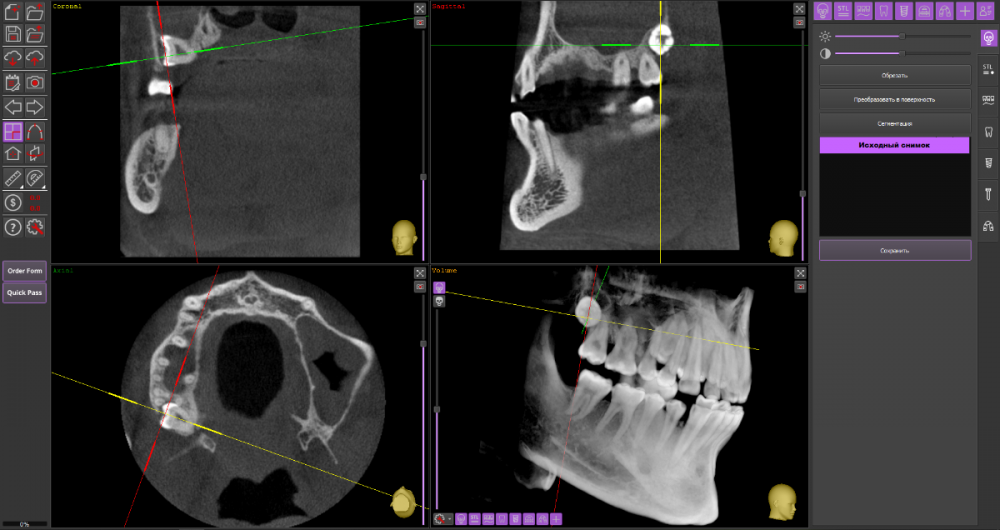

Mnrg Опубликовано 6 июля, 2023 Поделиться Опубликовано 6 июля, 2023 Всех приветствую! Беспокоит правосторонний гайморит и тонзиллит. Сделали КТ, нашли восьмерку, но предложили вместо удаления восьмерки депульпировать шестерку, консилиум сошелся во мнении, что корень перфорирует пазуху и пломба слишком близко к нерву, возможно воспаление. При зондировании между 6 и7 слегка побаливает десна, шестерка не беспокоит, холод чувствует, но не болит. Восьмерку предложили оставить. Спорить не стал, лишь решил собрать воедино мнения специалистов, т.к ближайшие более менее нормальные клиники от 100км. Архив с файлами КТ прикрепил, прошу специалистов глянуть и поделиться мнением, с чего все-таки начать, помочь разобраться.Archive.rar Ссылка на комментарий

wladdX Опубликовано 7 июля, 2023 Поделиться Опубликовано 7 июля, 2023 (изменено) Гайморит у вас совершенно необязательно имеет одонтогенную природу (вызван зубами). Судя по КТ, зуб 16 может быть виновником (а может и не быть). Для уточнения нужна также проверка витальности его пульпы (жив нерв или нет). Если пульпа нежизнеспособна, то этот зуб почти наверняка поддерживает воспалительный процесс в пазухе. Зуб 18 вряд ли нужно трогать. Лежит он себе в кости и пускай, никому он там не вредит. Да он вплотную прилежит к корням зуба 17, но и только. С внешней средой не контактирует. Никакого негативного влияния на соседние зубы он оказывать не должен: формирование корней завершено, потенции к росту и какому-либо движению нет. Удаление зуба 18 в данной ситуации вряд ли оправдано. Процедура не самая простая, но и не запредельной сложности. Изменено 7 июля, 2023 пользователем wladdX Ссылка на комментарий

Mnrg Опубликовано 7 июля, 2023 Автор Поделиться Опубликовано 7 июля, 2023 6 минут назад, wladdX сказал: Гайморит у вас совершенно необязательно имеет одонтогенную природу (вызван зубами). Судя по КТ, зуб 16 может быть виновником (а может и не быть). Для уточнения нужна также проверка витальности его пульпы (жив нерв или нет). Если пульпа нежизнеспособна, то этот зуб почти наверняка поддерживает воспалительный процесс в пазухе. Зуб 18 вряд ли нужно трогать. Лежит он себе в кости и пускай, никому он там не вредит. Да он вплотную прилежит к корням зуба 17, но и только. С внешней средой не контактирует. Никакого негативного влияния на соседние зубы он оказывать не должен: формирование корней завершено, потенции к росту и какому-либо движению нет. Удаление зуба 18 в данной ситуации вряд ли оправдано. Процедура не самая простая, но и не запредельной сложности. Шестерку проверяли холодом - чувствует, не знаю, означает ли это жизнеспособность пульпы, но на холод реагировал немного сильней других зубов. Сегодня открыл КТ программой RadiAntViewer и обнаружил в 3D просмотре визуальные признаки нахождения части восьмерки в краю пазухи. Конечно я не могу утверждать, т.к не врач и насколько понимаю это режим моделирования, но все же выглядит убедительно на мой скромный взгляд. Еще один глупый вопрос, если позволите) Возможно ли в шестерке в одном из трех корней воспаление и нерв разрушен, а другие два при этом будут создавать чувствительность, т.е быть "живыми" или же это фантастика? Деньги запросили немалые для нашего региона за депульпацию (13к) поэтому пытаюсь собрать как можно больше информации прежде, чем принимать решения. Ссылка на комментарий

wladdX Опубликовано 8 июля, 2023 Поделиться Опубликовано 8 июля, 2023 Ничего нового добавить к своим словам я не могу. Разве что повторить : "Гайморит у вас совершенно необязательно имеет одонтогенную природу". Т.е. надо рассматривать возможность ЛОР-патологии в чистом виде. Если зуб 16 с живой пульпой, то других одонтогенных причин при помощи данного КТ исследования я не вижу. На истину в последней инстанции не претендую. 1 1 Ссылка на комментарий